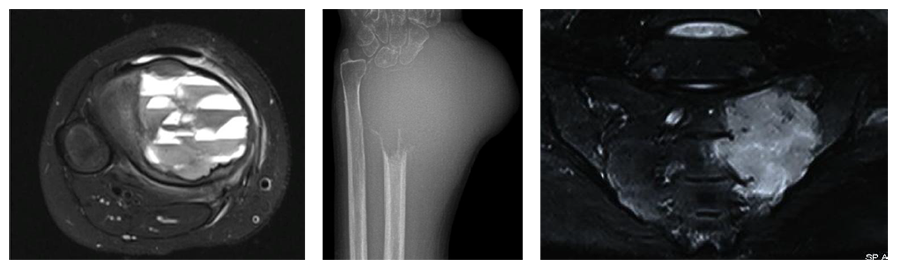

Bone tumors are rare lesions. A large part of these tumors are benign lesions, and they often occur by chance during radiological examinations for another reason. As a complaint, they usually show swelling and pain. Rarely, it is diagnosed after causing a fracture in the place where it was. Osteoid osteoma, osteochondroma (exostosis), enchondroma, non-ossifying fibroma, eosinophilic granuloma, simple bone cyst, fibrous dysplasia and intraosseous lipoma/ganglion are the most common lesions of benign tumors.